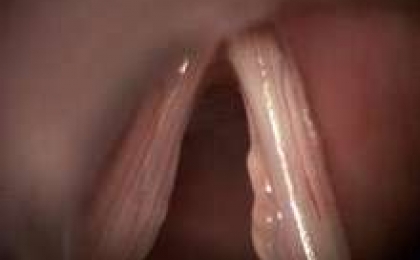

Vokal kordlar üzerinde oluşan kitleler, kordların atrofik problemleri ve kas yetersizliklerinin oluşturduğu ses problemleri “organik disfoni” olarak tanımlanmaktadır.